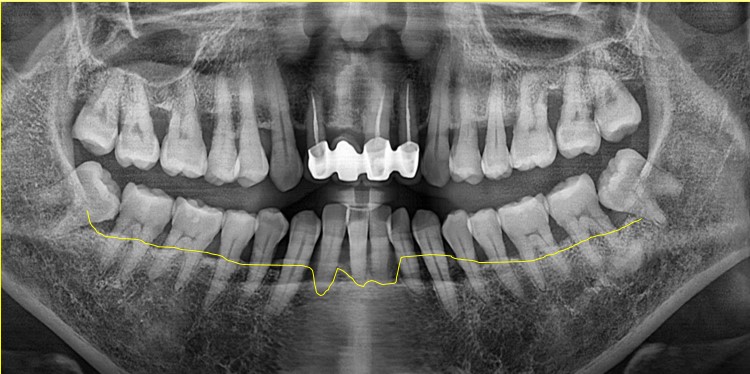

▲ 초진 파노라마

노란색으로 표시 된 선을 보시면 치주가 좋지 않아 전체적으로 잇몸이 내려 앉았지만

특히 앞니 부분에 잇몸이 많이 패여 있는것을 보실 수 있습니다.

# 42 41 #31 32 치아는 흔들림이 심해 발치 후 임플란트 치료와 #42 41 치아쪽에는

뼈이식도 함께 진행 하였습니다.

#43 33 치아는 신경치료 이후 크라운치료로 마무리 하였습니다.